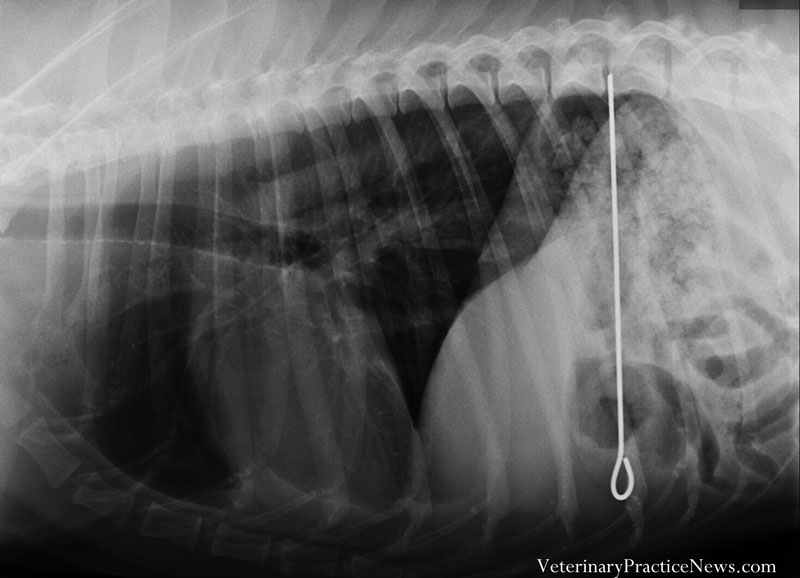

亞軍:遺失的烤肉串針

馬利是一隻容易惹上麻煩的德國短毛指示犬,這一次馬利來看獸醫時,牠的主人表示馬利可能吞了一根烤肉串針,事發當時她離開了正在準備的兩根烤肉串一會兒,回來時烤肉串和馬利都不見了。

後來她在床底下發現馬利與一根烤肉串針,另一根卻不翼而飛。經過檢查,那根針果然在馬利的胃裡,手術相當順利,馬利很快就恢復了,並且準備開始牠的下一個冒險。